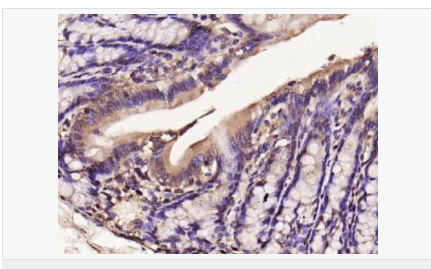

image.png